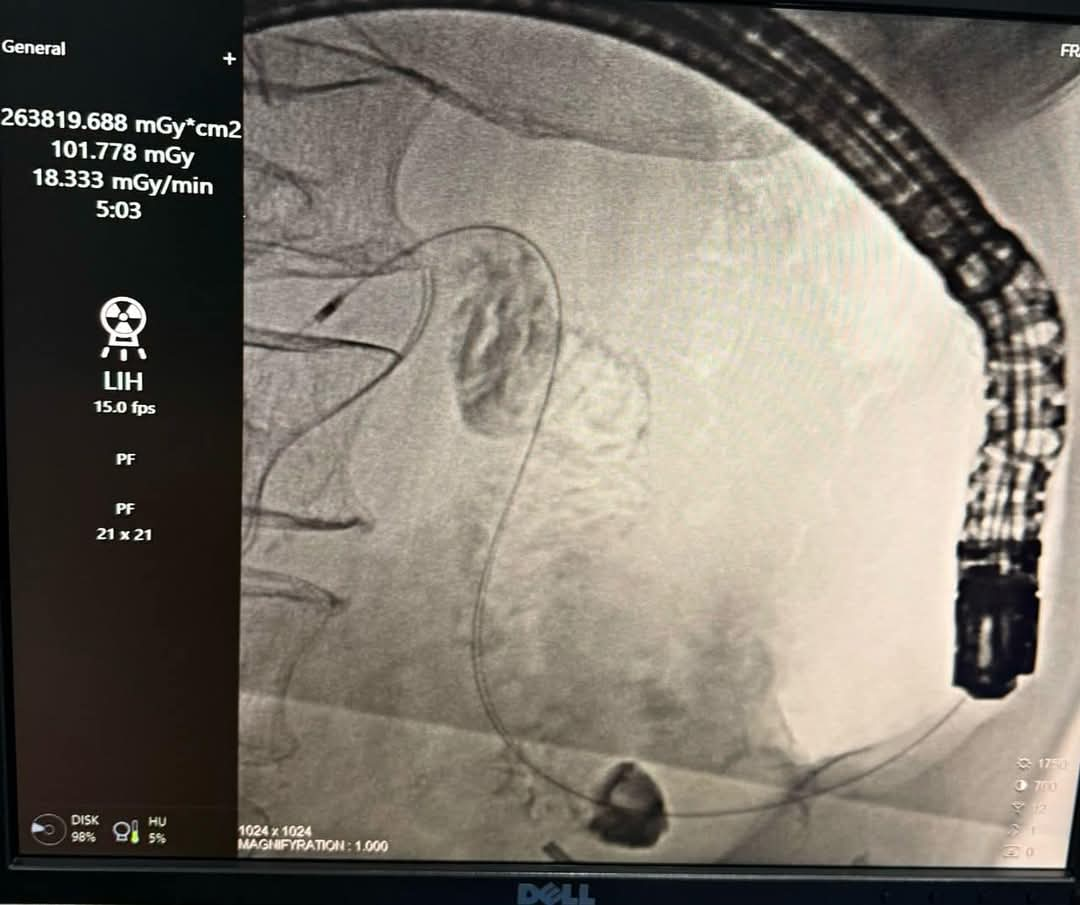

В Государственном учреждении «Республиканский научный центр хирургии сердца и сосудов» впервые в истории республики успешно выполнена малоинвазивная эндоскопическая стентировка пилородуоденального перехода. Операция проведена у пациента с опухолью антрального отдела желудка, вызвавшей стеноз привратника и нарушение прохождения пищи из желудка в кишечник, сообщает пресс-служба Минздрава и соцзащиты населения РТ.

Сарбон Мусоев, заведующий отделением диагностики и лечения Центра, возглавивший операцию, рассказал, что установлен металлический стент типа SEMS (Self‑Expandable Metal Stent) с расширяющимися свойствами. Новая технология позволяет восстановить полноценный пищевой тракт и облегчить состояние пациентов с неоперабельными опухолями желудка и поджелудочной железы, а также при тяжелых доброкачественных стенозах, сопровождающихся язвенными или ишемическими изменениями.

«Операция выполнена под контролем эндоскопии и рентгеноскопии в строгом соответствии с международными стандартами минимально инвазивной хирургии. Благодаря высокоточному оборудованию и использованию современных стентов мы смогли значительно улучшить качество жизни пациента», — отметил С. Мусоев.